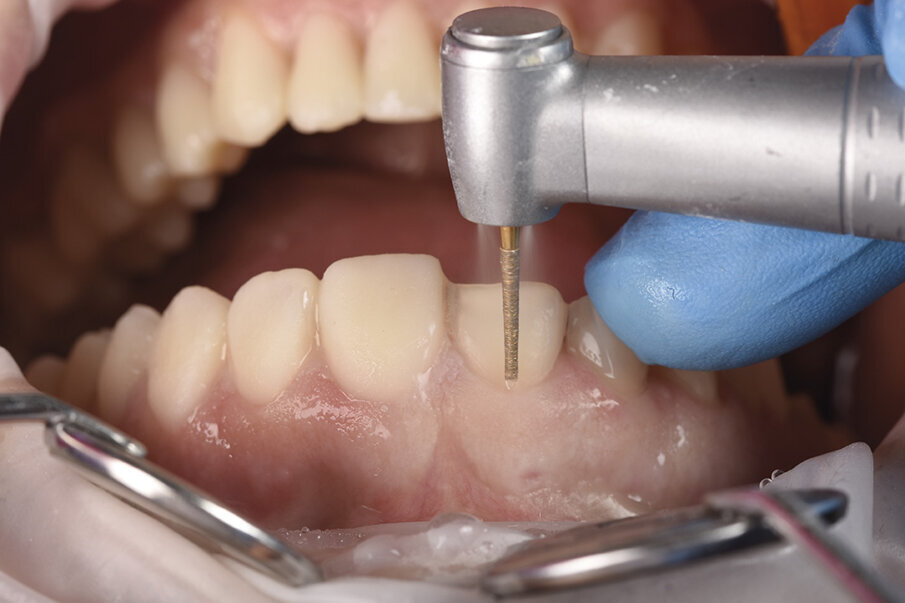

9. Brušenje zuba preko mock up-a (Sl. 12 ), omogućava kontrolu dubine preparacije, obezbeđivanje laboratoriji dovoljno prostora da uz ujednčenu debljinu keramike postigne uniformaopticki efekat nadoknada u celini.

10. Otisak za laboratorijske privemene nadoknade koje pacijent terapijski nosi 2-6 meseci (Sl. 13). Proces navikavanja kao i potreba za eventualno reevaluacijom determinisane nove VDO najsigurnije je obaviti u ovoj fazi. U tom periodu